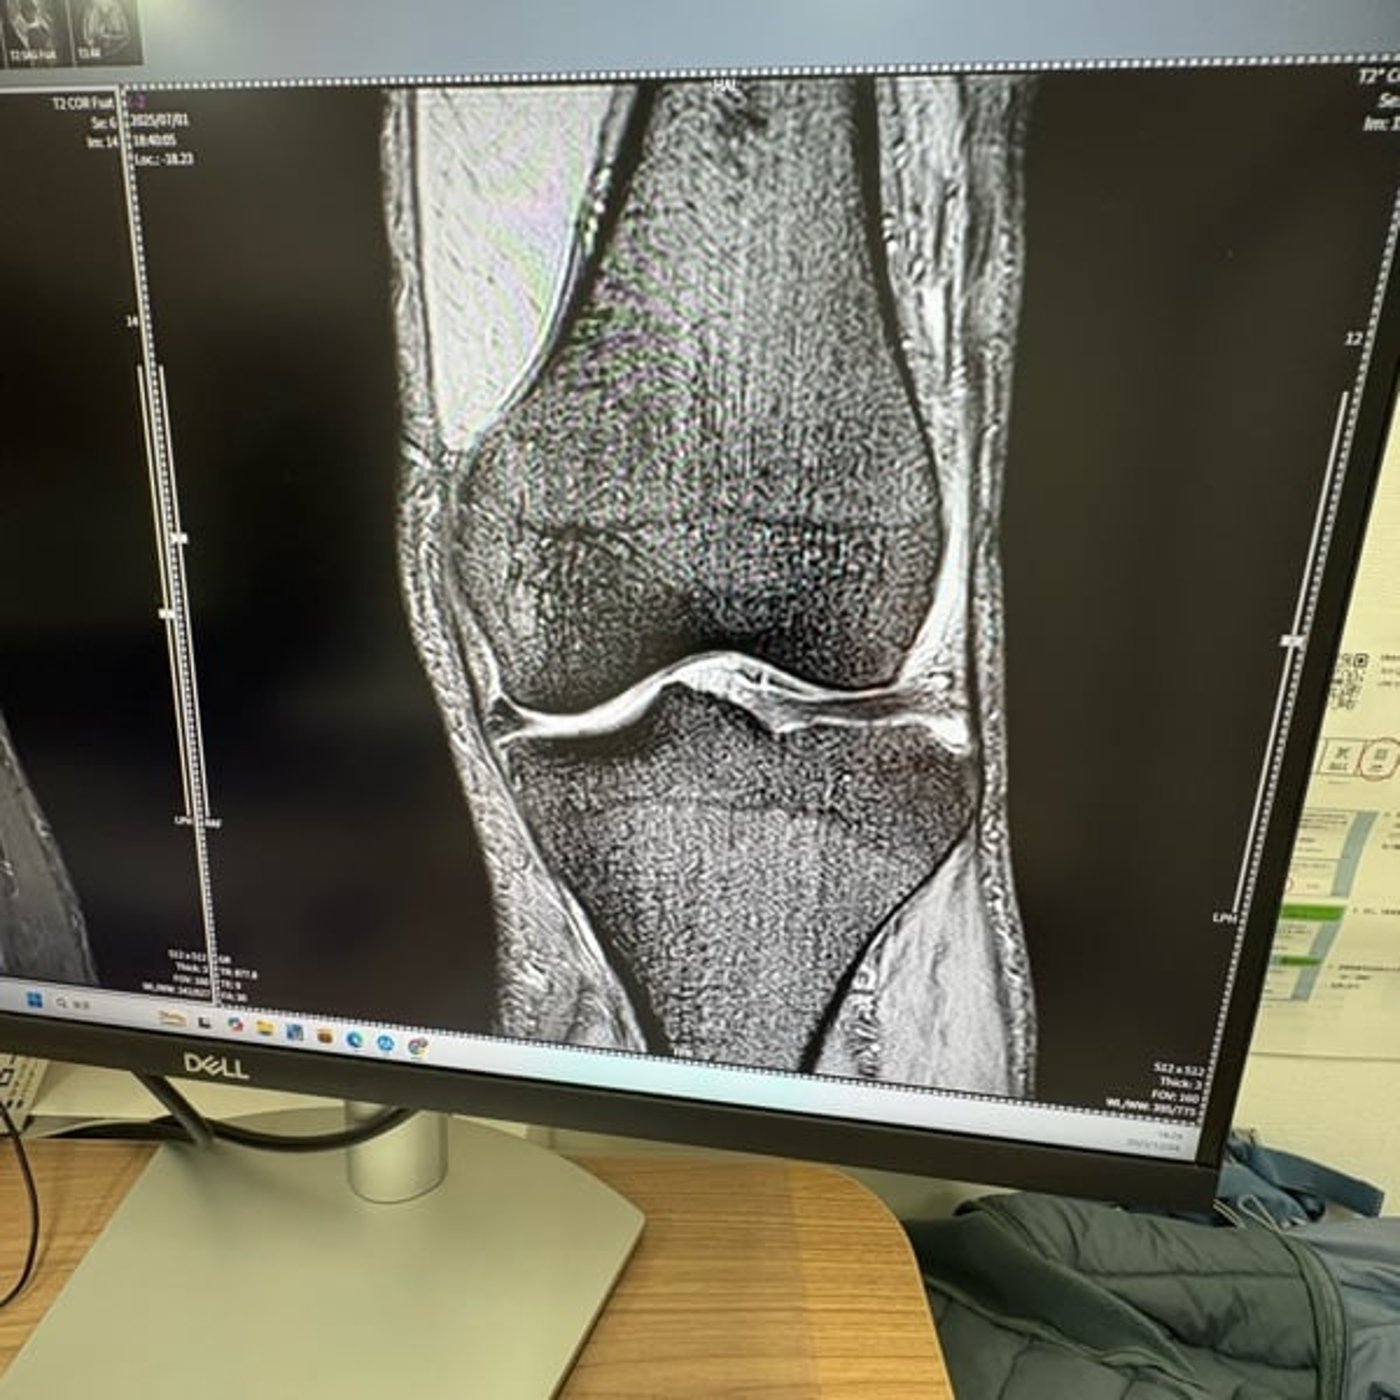

今日のラジオ📻は昨夜整形外科受診した時の待ち時間に画面に出ていた膝の画像をチャッピーさんに見せみた結果についてです。

#画像診断